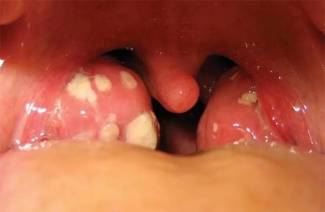

Plesňová tonzilitída u dieťaťa a dospelých - príčiny, prvé príznaky a prejavy, liečba

Plesňové ochorenie mandlí je ťažké odhaliť v raných štádiách, čo môže viesť ku komplikáciám alebo k prechodu choroby do chronickej formy ...